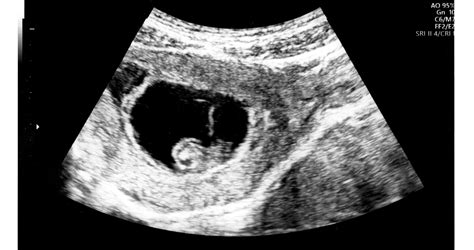

A vetélés a korai terhességben gyakori; az első trimeszter során a terhesség elvesztése az igazolt terhességeknél körülbelül 10-25%. Általában azt gondolnánk, hogy a vetélés mindig erős vérzéssel, erős fájdalommal jár, eszünkbe sem jutna, hogy néha a vetélés tényét csak egy ultrahangvizsgálat során tudjuk megállapítani. Ezt az esetet „missed abortion”-nak hívjuk, vagyis olyan vetélés, amikor a terhesség fejlődése megszakad, nem látunk az embriónál szívműködést, de a vetélés folyamata nem indul be.

A missed abortion diagnosztizálása általában ultrahangvizsgálat segítségével történik, amely kimutatja, hogy a terhesség fejlődése megállt, és nem látható szívműködés. A vákumaspiráció egy modern és biztonságos eljárás, amely során a méhben maradt terhességi szöveteket eltávolítják. A beavatkozás rövid altatásban történik, így a páciens nem érez fájdalmat vagy kellemetlenséget. Fontos megjegyezni, hogy a korábban gyakran alkalmazott küret (kanállal történő beavatkozás - kaparás) ma már nem ajánlott, mivel magasabb a szövődmények kockázata.